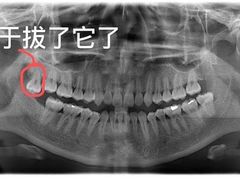

• 瑞尔齿科(颐堤港诊所)

哈哈哈老加菲 | 20-07-24

• -瑞尔齿科(颐堤港诊所)